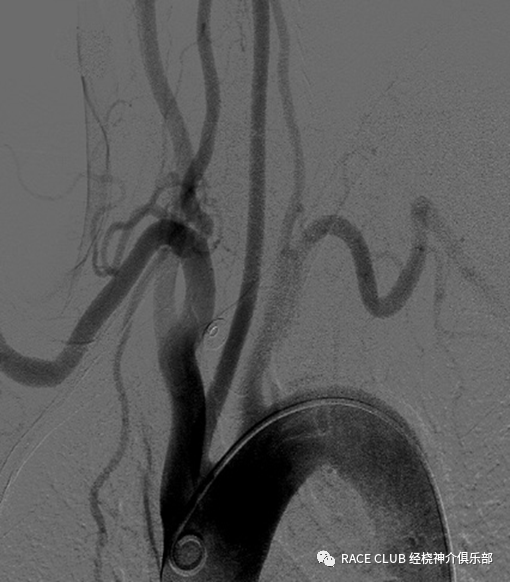

弓上造影(经桡动脉)

造影导丝是什么全脑血管造影术_https://www.jmylbn.com_新闻资讯_第24张

1.做完弓上造影边后撤猪尾导管,边旋转,头端朝向左侧成“6”字型

2.进260cm导丝入降主动脉至腹主动脉

3.稳住导丝,撤掉猪尾导管

造影导丝是什么全脑血管造影术_https://www.jmylbn.com_新闻资讯_第25张

4.沿导丝送入西蒙导管,至大弯完全进入降主动脉

5.撤掉260cm导丝

6.退导管至大弯的顶点顶在弓上,边退边顺时针旋转导管

造影导丝是什么全脑血管造影术_https://www.jmylbn.com_新闻资讯_第26张

7.把导管转成“8”形

8.前推导管,导管头端会弹入左锁骨下动脉,稍回撤导管,让导管头端进入左锁骨下动脉,冒烟、摆体位,造影

9.左锁骨下动脉造影完后,前推导管,导管弹入左颈总动脉,稍后退导管,让头端头端进入左颈总动脉,冒烟后,摆体位造影

造影导丝是什么全脑血管造影术_https://www.jmylbn.com_新闻资讯_第27张

10.前推导管,并旋转,使头端弯曲朝向右侧,后撤导管,使头端进入头臂干

11.边退边旋转导管,使其弯曲头端朝向右颈总动脉

12.继续后退进入右颈总动脉,冒烟,摆体位,造影

造影导丝是什么全脑血管造影术_https://www.jmylbn.com_新闻资讯_第28张

13.右颈总动脉造完影,进导丝,后撤导管

14.当导管撤至头臂干,撤掉导丝,缓慢后退导管入右锁骨下动脉至右椎动脉开口附近,冒烟,摆体位造影